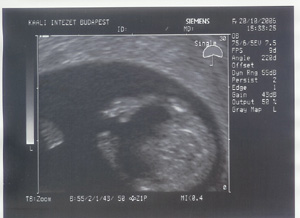

A te mensidnek viszont nagyon örülök. Drukkolok a mai vizsgálathoz. Az UH vizsgálatok nem ártanak a szervezetednek, emiatt ne félj. Még az sem igazolt, hogy a babának árt a sok UH.